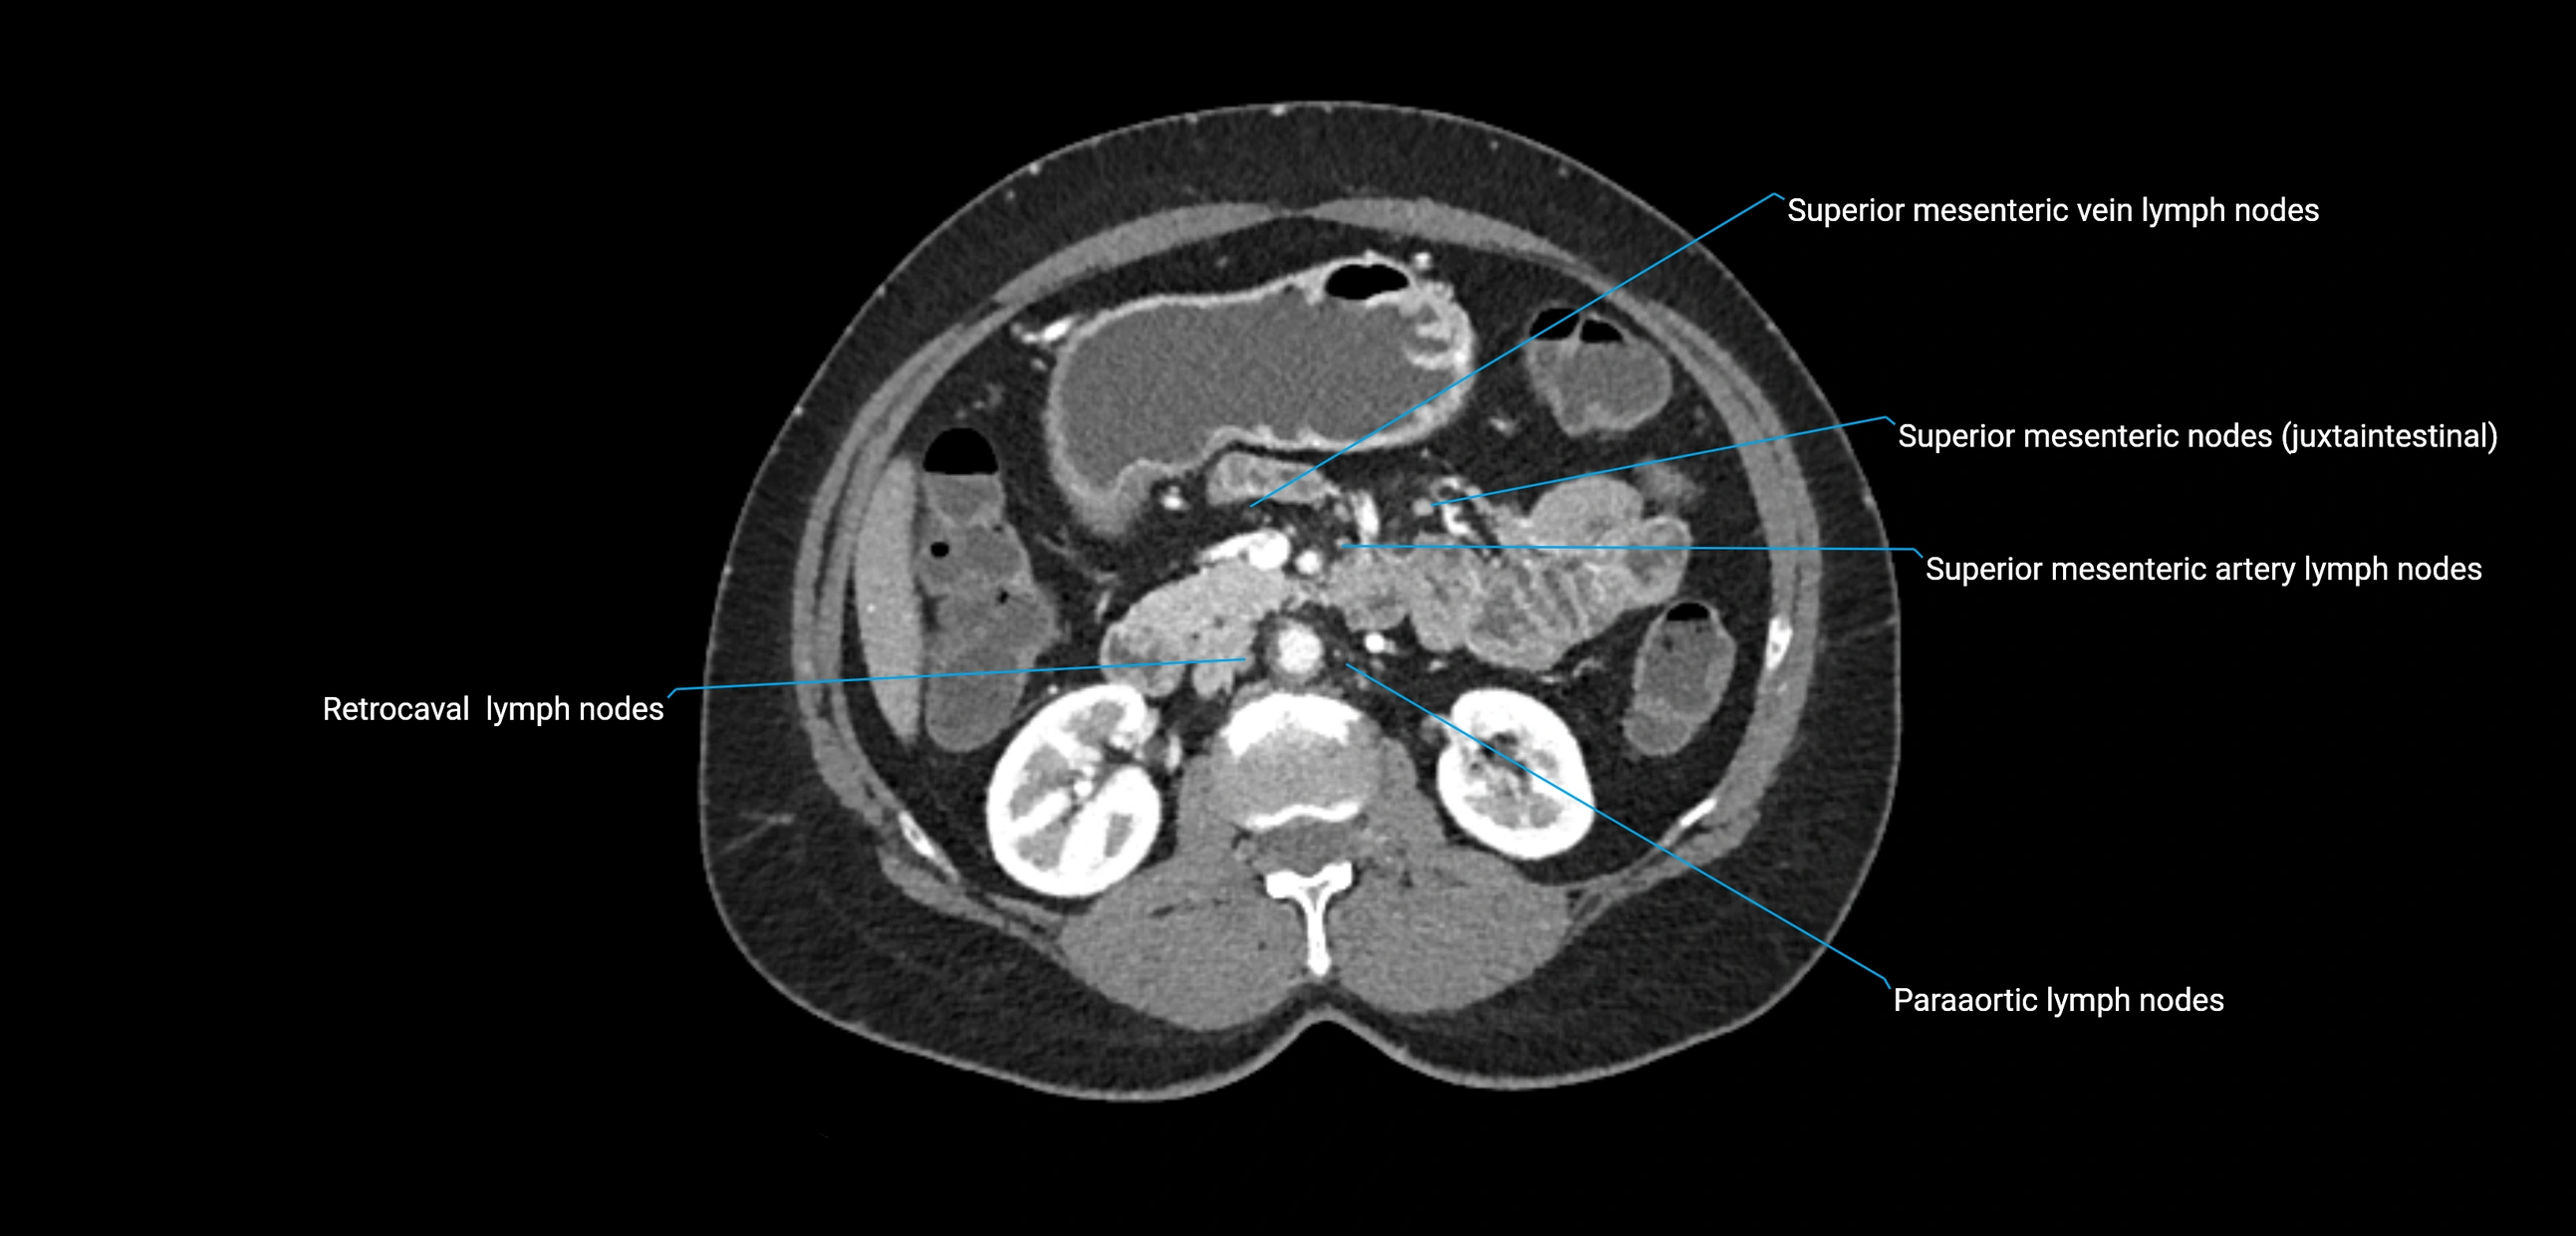

CT Appearance

CT Pre-Contrast:

• Nodes appear as soft-tissue density nodules adjacent to the aorta and IVC

• Calcification may be seen in chronic infections (e.g., tuberculosis)

CT Post-Contrast:

• Normal nodes enhance homogeneously

• Malignant nodes may show heterogeneous enhancement, central necrosis, or conglomerate formation

• Size >1 cm short axis is suspicious, though morphology and distribution are equally important

CT Venography (CTV):

• Demonstrates nodal encasement or compression of adjacent vessels (aorta, IVC, renal veins)

• Useful in staging testicular and ovarian malignancies

• Provides 3D reconstructions for retroperitoneal lymph node dissection planning